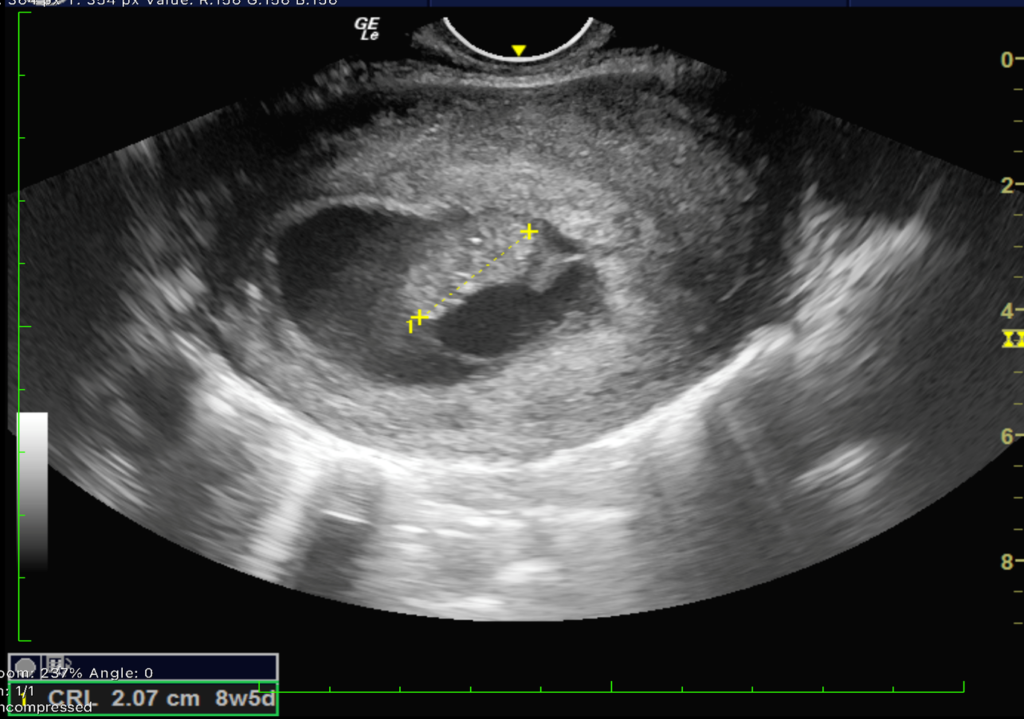

We report a case of a 24-year-old lady who was unable to conceive for a period of 8 years. Infertility workup was negative. In 2018, she conceived, however cardiac activity was not demonstrated in the fetus and eventually medical abortion was performed. Transvaginal sonography was performed for the same at a private center which did not pick up any uterine structural abnormality. In 2021, the patient presented to our emergency department with a 14-week gestation pregnancy with complaints of bleeding per vaginum for 2 days. Antenatal transvaginal ultrasound was performed for confirmation and viability of an intrauterine pregnancy. An intrauterine gestational sac with crown rump length corresponding to 8 weeks 5 days and absent cardiac activity was seen suggesting the diagnosis of missed abortion (Figure 1). Surrounding the gestational sac was fluid with internal echoes suggesting failure of implantation (Figure 2). A well-defined uniformly echogenic pedunculated lesion was seen in the endometrial cavity (Figure 3). As it was traced towards the point of its origin, a focally hypoechoic region was demonstrated interrupting the hyperechoic endometrial lining (Figure 4), classically described as the ‘interrupted mucosa sign’ [2]. On colour doppler image, a single vascular pedicle was demonstrated (Figure 5), known as the ‘pedicle artery sign’ [3]. Based on these classical features the diagnosis of an endometrial polyp was made. It was seen to abut the gestational sac suggesting mechanical hindrance to growth of the embryo (Figure 6). On real time imaging, the endometrial polyp was seen prolapsing from towards the uterine fundus to the lower uterine segment (Figure 7). For better characterization of the endometrial polyp, it has been recommended to distend the uterine cavity with saline (also known as saline infusion sonohysterography) [4,5], however in our case it was unwarranted because the gestational sac and fluid naturally distended the uterine cavity and helped in optimum visualization (Figure 4,6). Figure 8 depicts another case of an endometrial polyp showing a non-gravid uterus with an echogenic lesion in the endometrial cavity showing the classical interrupted mucosa sign (Figure 8A) and the feeding artery sign (Figure 8B).

Figure 1. Transvaginal sonography shows an undifferentiated fetal pole with absent cardiac activity corresponding to 8week 5 days in a 14 week gestational pregnancy calculated from last menstrual period.